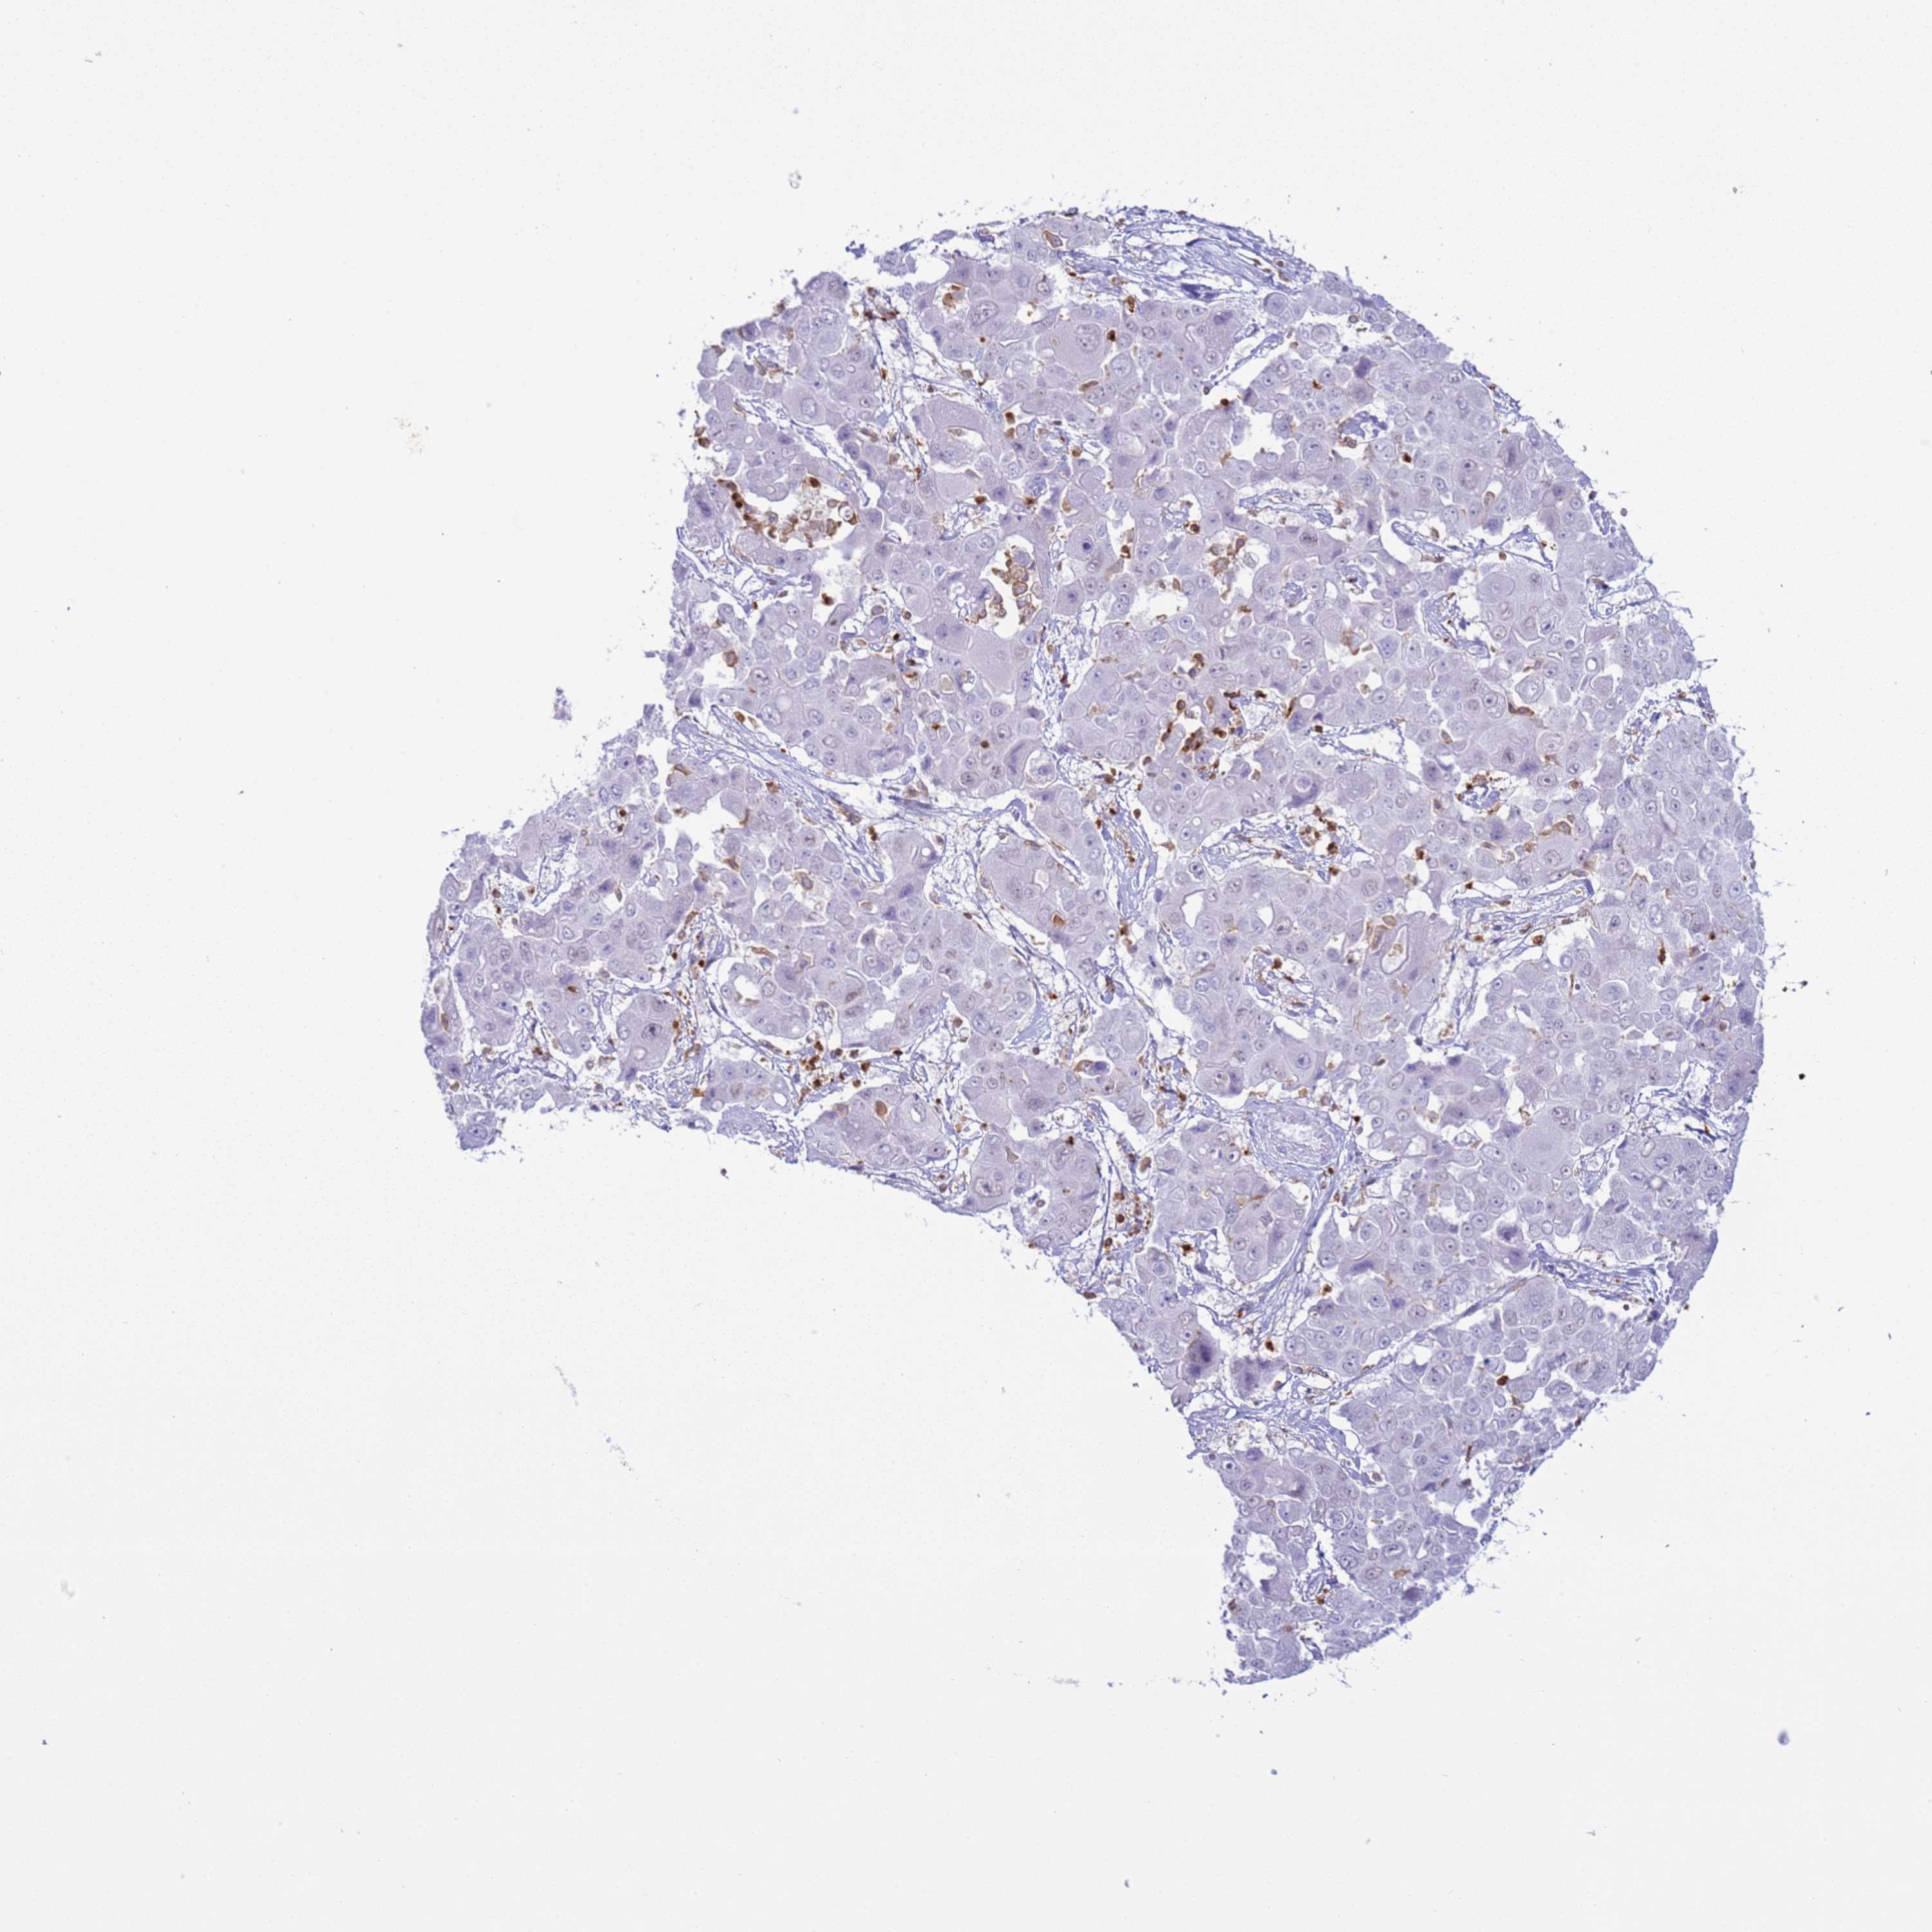

LIVER CANCER - Protein expressioni

A mouse-over function shows sample information and annotation data. Click on an image to view it in a full screen mode. Samples can be filtered based on level of antibody staining by selecting one or several of the following categories: high, medium, low and not detected. The assay and annotation is described here.

Antibody stainingi

Antibody staining in the annotated cell types in the current human tissue is reported as not detected, low, medium, or high, based on conventional immunohistochemistry profiling in selected tissues. This score is based on the combination of the staining intensity and fraction of stained cells.

Each image is clickable and will lead to virtual microscopy that enables deeper exploration of all samples and also displays staining intensity scores, fraction scores and subcellular localization as well as patient and tissue information for each sample.

Antibody HPA046700

Antibody HPA076024

Staining

High

Medium

Low

Not detected

Intensity

Strong

Moderate

Weak

Negative

Quantity

>75%

75%-25%

<25%

None

Location

Nuclear

Cytoplasmic/membranous

Cytoplasmic/membranous,nuclear

Cholangiocarcinoma

Carcinoma, Hepatocellular, NOS